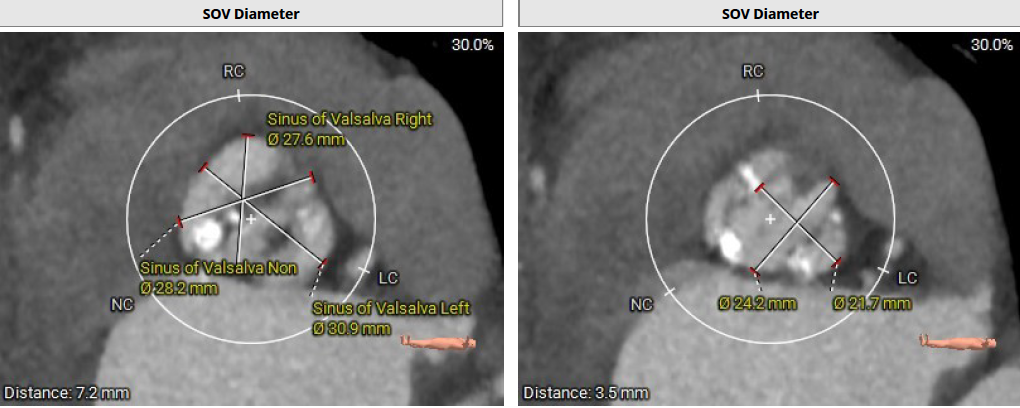

患者Type1 二叶瓣,右无融合,融合嵴钙化,钙化主要分布瓣叶缘和融合嵴处,无冠窦底钙化向下延伸至流出道4mm处。Annulus面积398mm²,LVOT面积400mm²,SOV 27.6-30.9mm,STJ高度21.3mm,内径29-32.7mm,瓣环角度62°,升主动脉扩张,左冠高度14.9mm,左冠瓣叶长度15.7mm,右冠高度15.8mm,右冠瓣叶长度9.2mm,模拟植入21#瓣膜VTC LCA 2.4mm,右侧髂内分叉处可见钙化,右侧髂外动脉最细为6.1mm,左侧髂外动脉最细为6.1mm,外周入路尚可。

瓣环:Annulus Dimensions - Area:398.2 mm² ;左室流出道(瓣下3mm)Area:400.5 mm²

窦宽:Distance L:30.9mm Distance R:27.6mm Distance N: 28.2mm

窦管交界:Area: 774.3mm² 、Mean Diameter:30.8mm;升主:Area: 1434.5mm²;Mean Diameter:42.7mm

850阈值下钙化积分为267mm³,钙化主要分布瓣叶缘和融合嵴,无冠窦底钙化向下延伸至流出道4mm。